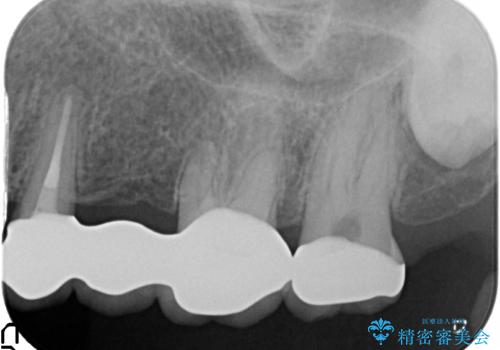

- 「老朽化し古くなった銀歯を白いものにやりかえたい。」と希望され来院されました。

銀歯の下には再発した虫歯やセメントの漏出が見られ、丁寧に除去したのちセラミックによるクラウン・ブリッジ補綴を行います。

- 66万円 仮歯 ジルコニアクラウン×6費用は治療当時の料金となります